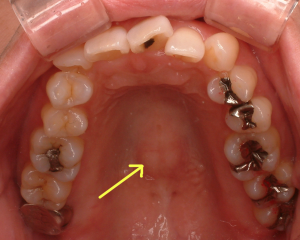

2016年に来院された時に撮影していたお口の中の写真を12年前の写真と比較すると、下顎の内側の骨の隆起が大きくなって発達してきています。これは噛み締めの習慣のある患者さんによく見られる現象です。

その他骨のところに現れるサインでは、上の顎の内側の真ん中が盛り上がってくることもあります。